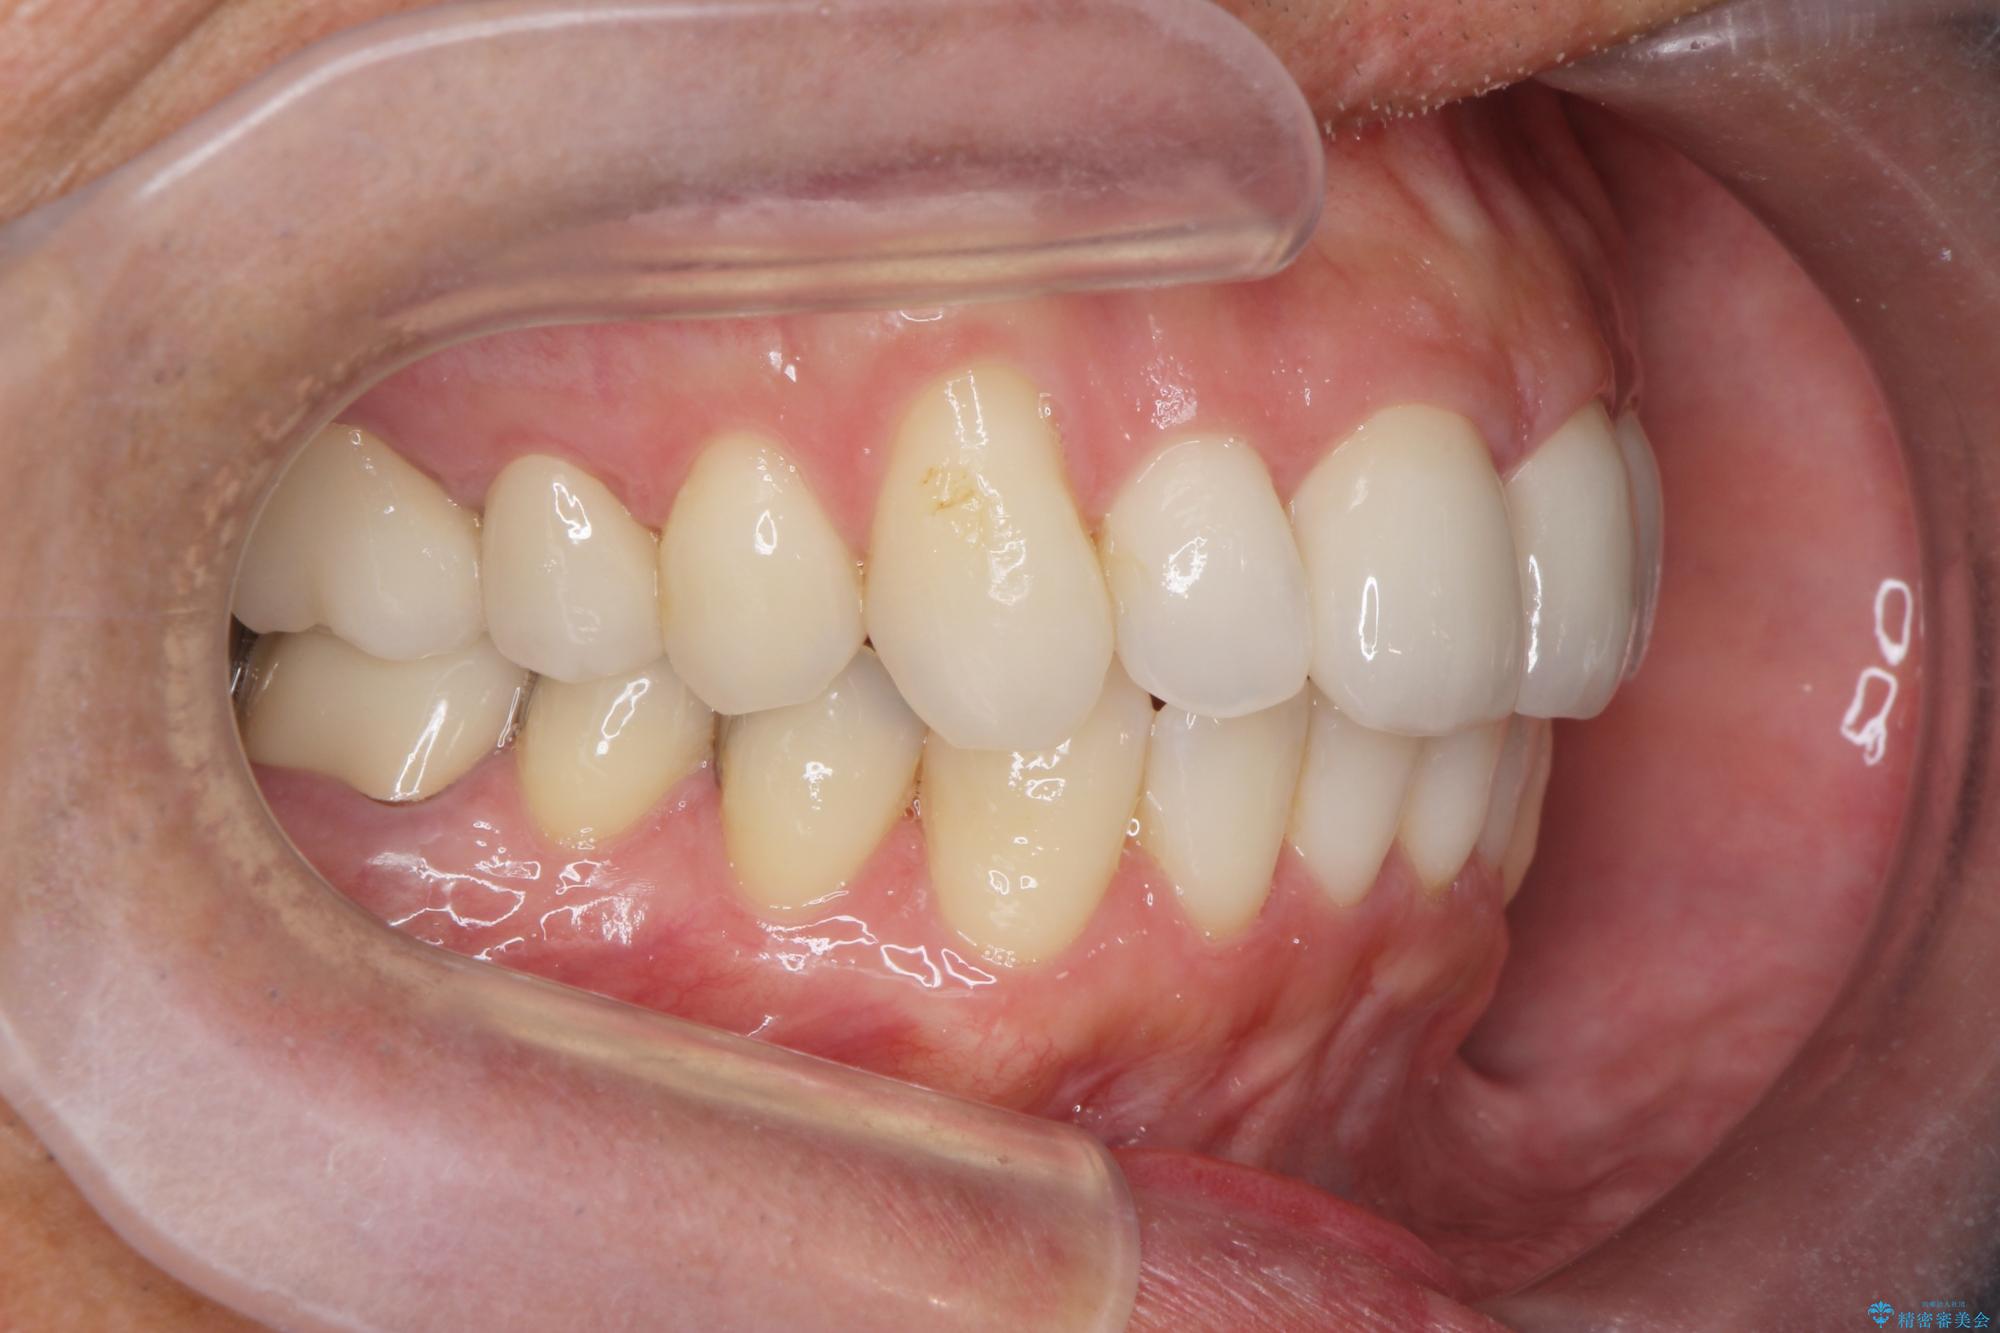

- 突き出た前歯の角度の改善と虫歯治療の改善を求めて来院されました。

虫歯を除去したのち、マウスピース矯正治療を行い、歯並びやがたつきを改善したのち、セラミックに置き換えることで審美性の向上を計画します。